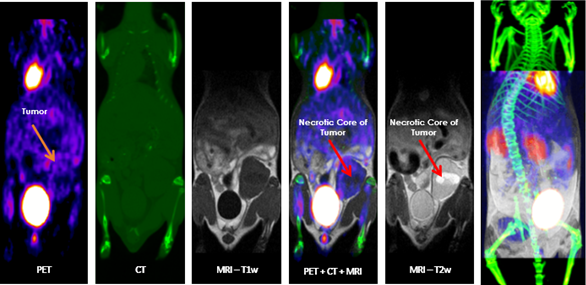

Multimodal Imaging: Multimodal imaging combines the strength of MRI with other imaging modalities such as PET and CT. PET provides information on the spatial distribution of molecular signal of interest. In this case MRI confirmed that the absence of tracer uptake in the center of the images was due to the presence of a necrotic core, which appears hyperintense on T2-weighted MRI. Image Credit: Scintica Instrumentation Inc

Multimodal imaging combines the strength of MRI with other imaging modalities, such as PET and CT. PET provides information on the spatial distribution of molecular signal of interest. In this case MRI confirmed that the absence of tracer uptake in the center of the images was due to the presence of a necrotic core, which appears hyperintense on T2-weighted MR. Image Credit: Scintica Instrumentation Inc